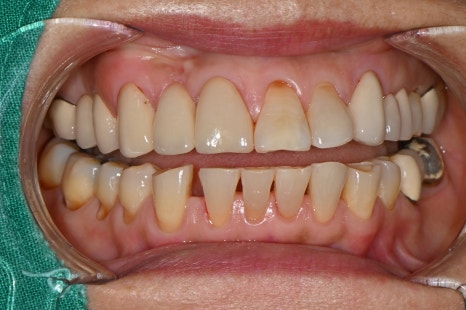

Intraoral photos at the first visit

➤ Initial examination findings

Before planning the aesthetic front tooth prosthetics and molar implant treatment, here is the patient's initial condition.

After a comprehensive diagnosis of tooth alignment, missing areas, and the condition of existing prosthetics, the following treatment plan was explained:

Right lower molar area (#45~47): We recommended removing the old bridge and making new crowns for #45 and #47, and for the empty space at #46, we recommended placing one implant instead of the existing bridge.

Front tooth area (#11): There was severe cervical wear, and additional prosthetic treatment was needed.

Lower front tooth area (#43, #42): The space between the teeth had widened, so we planned an aesthetic improvement using crowns.